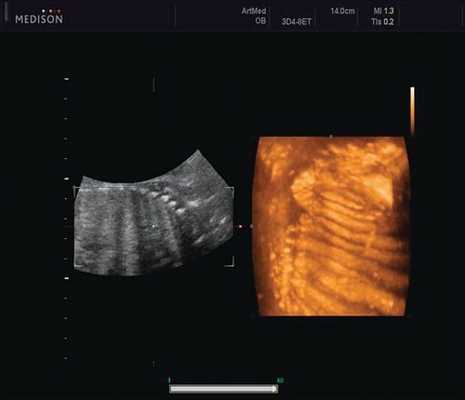

Клиническое наблюдение 1

Пациентка К., 26 лет, обратилась в клинику в 23 нед беременности. Беременность первая. Исследование проводилось на аппарате Accuvix-XQ (Samsung Medison) с использованием режима поверхностной объемной реконструкции 3D/4D. Показатели фетометрии полностью соответствовали сроку беременности. В процессе сканирования позвоночника во фронтальной и сагиттальной плоскостях выявлена угловая деформация позвоночника в грудном отделе, протяженностью около трех позвонков. В поперечной плоскости сканирования нарушения структур и целостности тканей не было обнаружено. В режиме 3D/4D реконструкции было выявлено асимметричное расхождение ребер правой и левой стороны грудной клетки (рис. 4).

Рис. 4. Эхографическая картина асимметрии ребер в режиме 3D реконструкции.

Ребра левой стороны были сближены, межреберные промежутки уменьшены по сравнению с противоположной стороной (рис. 5, 6). Другой патологии у плода не было выявлено. Заподозрен врожденный сколиоз, основой которого является наличие боковых полупозвонков (hemivertebrae) или боковых клиновидных позвонков. В 26 нед ультразвуковая картина сохранялась. При проведении трехмерной эхографии получено отчетливое изображение асимметрии реберных дуг и сколиотическая деформация позвоночника.

В 30 нед фетометрические показатели плода соответствовали сроку беременности. Сколиотическая деформация позвоночника сохранялась. Дополнительно выявлена оболочечная грыжа, исходящая из грудного отдела позвоночника, в области деформированных позвонков. Грыжа представляла собой стебельчатой формы образование с суженной ножкой (рис. 7, 8). Концевая часть ее была расширена в виде петли и заполнена анэхогенным содержимым (ликвором), которое отчетливо дифференцировалось на фоне "мутных" околоплодных вод (рис. 9). Таким образом, диагноз был уточнен: spina bifida - менингоцеле.